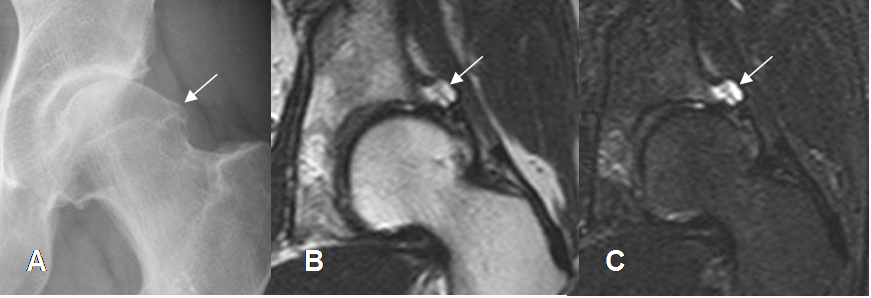

Fig 115. Quiste paralabral.

A: Rx AP. Prominencia del borde lateral de la cebaza femoral, por pinzamiento tipo cam.

B: RM coronal en T2 y C: RM coronal en STIR. Imagen quística e hiperintensa en ambas secuencias, hacia la región superoexterna del reborde acetabular, que corresponde a quiste paralabral.